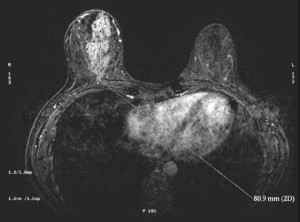

En la RM que se hizo a nuestra paciente, se puede visualizar la lesión hiperintensa en la mama derecha.

Tras la sospecha de cáncer por las pruebas anteriores, lo más oportuno es realizar una resonancia magnética. Está indicada en la estadificación del cáncer de mama, caracterización de lesiones indeterminadas con otras pruebas y determinación de la multifocalidad o multicentridad del tumor.

La RM aporta mucha información en este caso y la radiofrecuencia que emite no es ionizante. Sin embargo, no sería la primera prueba indicada tras los hallazgos clínicos, por ser una técnica más complicada, cara y de mayor duración.